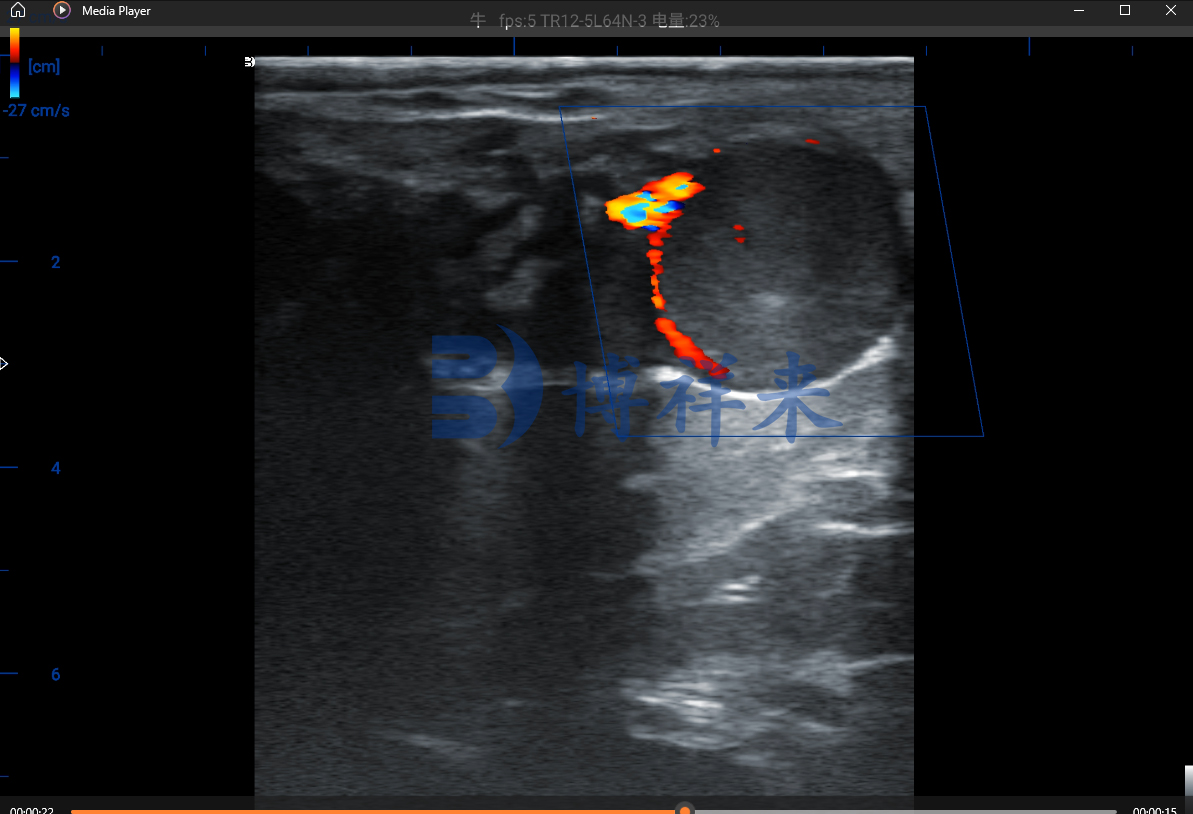

正因为黄体血流在“妊娠”与“未妊娠”之间呈现出截然不同的影像特征,多普勒超声才能够在21天这一极早期阶段捕捉到差异。影像中的妊娠黄体通常轮廓清晰、质地均匀,并且周边能看到连续而丰富的彩色血流信号;而未妊娠黄体则显得松散、回声不均匀,血流断续甚至完全看不到。

在实际检测过程中,AI会自动捕捉卵巢区域的结构特征,根据黄体的大小、形态、边界完整性以及血流灌注强度,给出早孕、疑似或未孕的提示。技术员不再需要依赖多年积累的影像经验,也不必担心人为误差导致的误判。即便是年轻的操作员,也能在短时间内掌握检测要领,把黄体血流变化判断得又快又准。